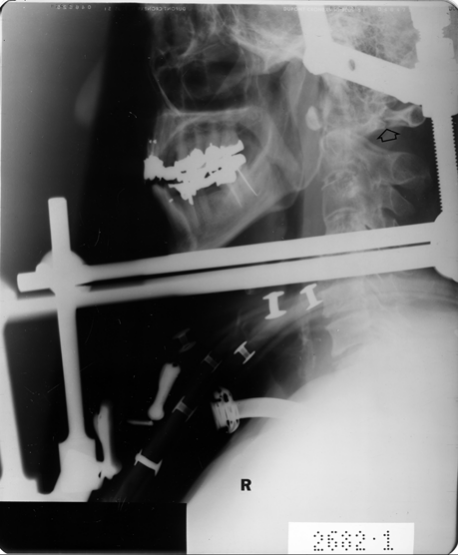

18

Q

What is the mechanism of a Jefferson fracture?

What evidence is there against a posterior arch fracture diagnosis?

ignore arrow

A

Axial compression

Halo brace (post halo reduction)

unstable fracture